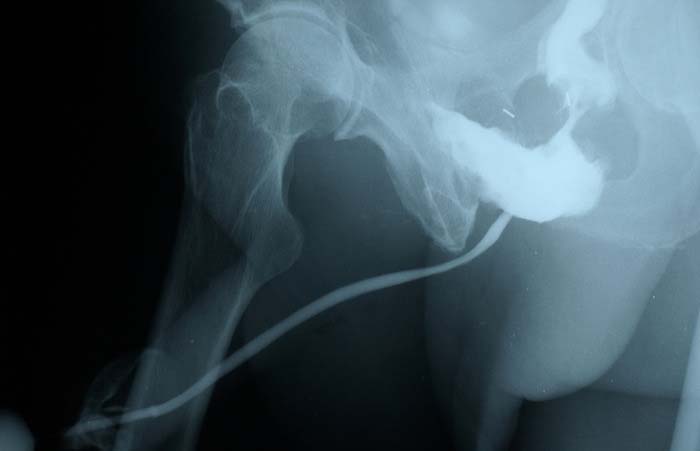

Fistulografía.

Consiste en introducir una pintura (medio de contraste) por el orificio externo de la fístula y después se toma una radiografía. Esto permite observar de forma indirecta todo el camino de la fístula hasta su origen en el intestino.